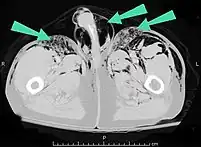

O enfisema pode produzir protuberâncias, como nódulos móveis com ruídos crepitantes a palpação. Em uma radiografia de tórax, o enfisema subcutâneo pode ser visto como estriações radioluzentes (escuras) nas áreas com músculos. O ar nos tecidos subcutâneos pode interferir na radiografia do tórax, potencialmente obscurecendo condições graves, como o pneumotórax. Também pode reduzir a eficácia do ultrassom.[8] Também é visível na tomografia e na ressonância magnética como bolhas escuras.